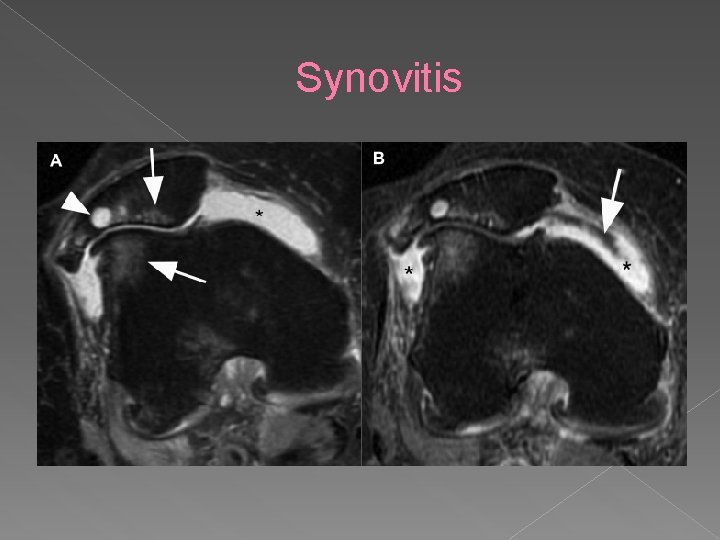

Synovitis